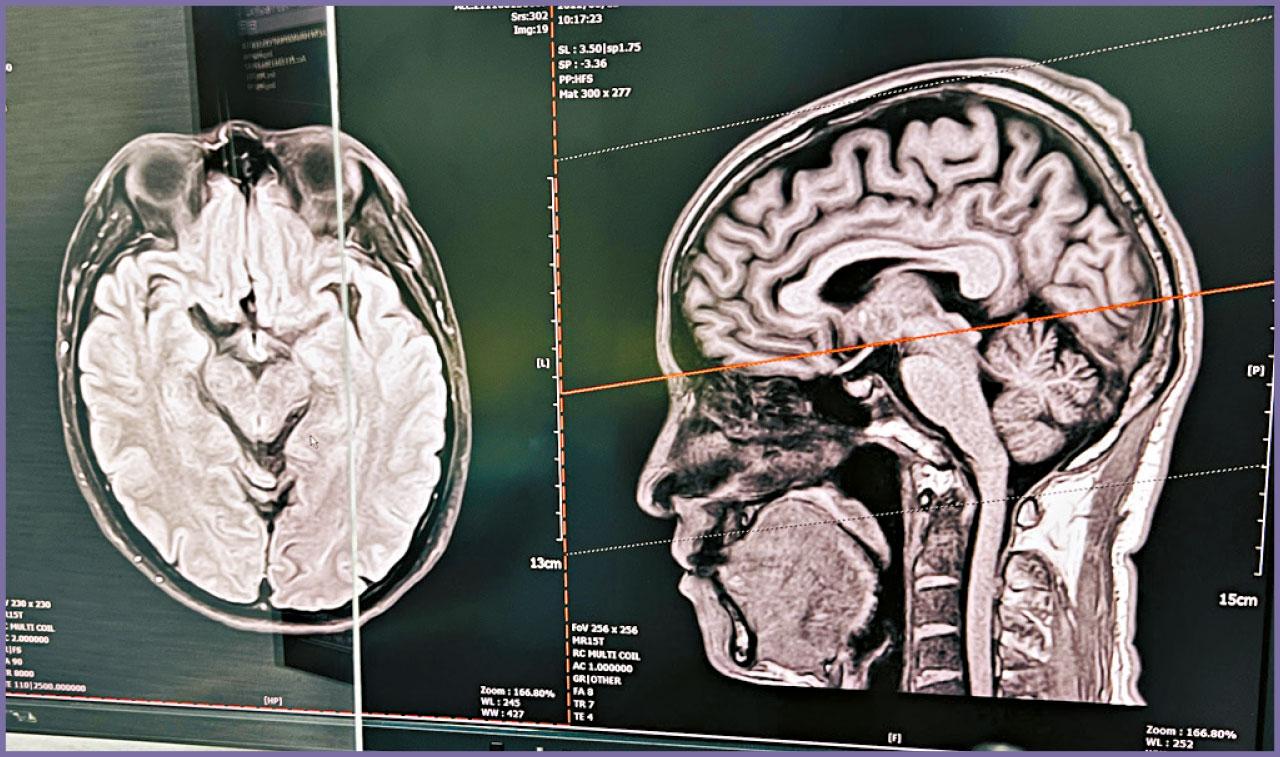

疫後社會全面復常,雖然政府鼓勵巿民外出消費,振興本地經濟,但每逢周末或長假期,香港人北上消費的熱潮卻有增無減。近期專誠往內地求診的病人亦愈來愈多,反映在經濟周期逆轉、兩地匯率變化下,巿民「身體最誠實」的醫療消費模式。其中本地醫生經常遇到的情況,就是病人帶同從內地照的磁力共振(MRI)報告來尋求第二意見(Second Opinion)。

到底往內地照MRI,有何利弊?從病人的角度來看,內地MRI的收費普遍較本地便宜得多,相信是消費者的首要考慮。其次,近年內地MRI的質素,與十多年前相比,的確有明顯提升。再者,高鐵與港珠澳大橋等千億造價的跨境交通基建,大大縮短往返中港時間,促進了兩地醫療產業的良性競爭和合作。最後,本身在內地出世、但現居本港的巿民,基於對祖國的深厚感情,也傾向往內地照MRI。

此外,內地的MRI報告,通常都只有簡體字版本,對於一直以英語受訓、不熟悉簡體字的醫生來說,或需要以翻譯軟件來協助理解報告內容。再者,撰寫報告的,既是內地放射科醫生專家,萬一在影像診斷上有任何錯漏,以致本地醫生基於報告而造成治療上失誤,法律責任屬誰卻是一大問號。更重要的是,當計劃較為複雜的手術時,例如需要在脊椎內植入金屬假體,醫生通常需要更多影像數據作術前評估,然而內地的MRI報告,卻通常沒有附上光碟或USB來讓醫生作詳細檢閱。故此,醫生或會建議病人在接受大型手術前,在本地再照一次MRI來覆檢,而病人在平衡利弊和風險下,都會欣然接受。